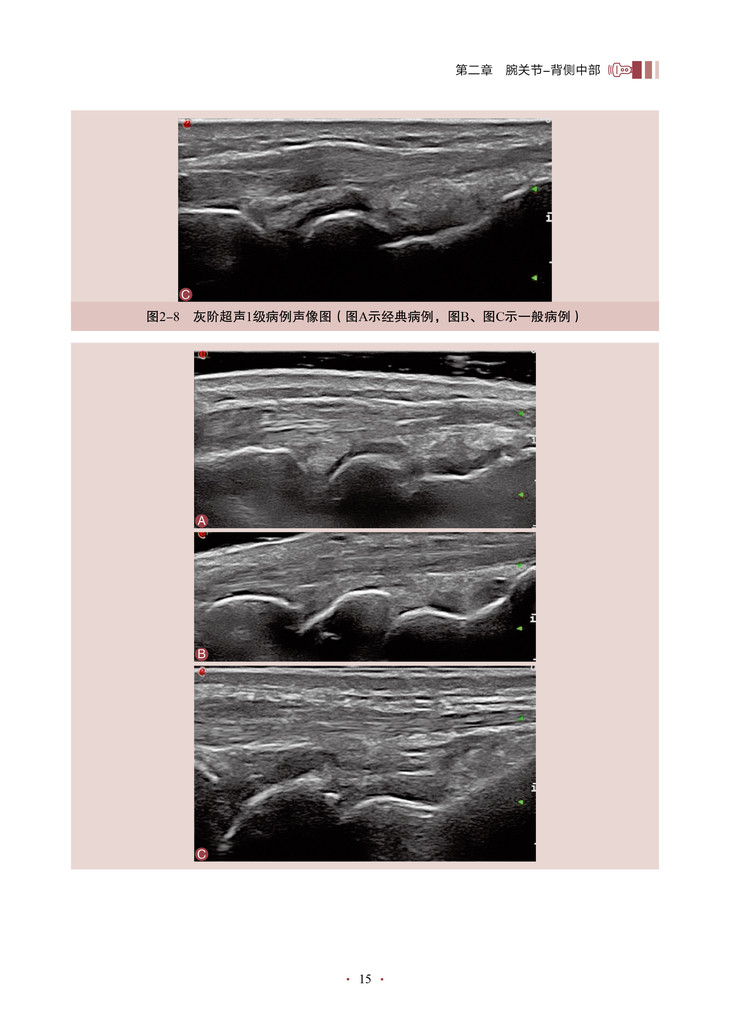

本书的核心内容是将超声技术应用于关节炎程度的评估,特别是对关节滑膜炎症的评分和客观量化。通过详细地介绍超声评分系统的构建和应用,作者为我们展示了一种全新的、基于客观指标的关节炎评估方法。该书深入探讨了关节滑膜超声图像的解读和分析,教导读者如何识别和评估关节炎引起的滑膜病变。通过使用可靠的超声评分系统,医师和研究人员能够更准确地量化关节炎患者的炎症程度和疾病进展,从而更好地指导治疗和监测疗效。